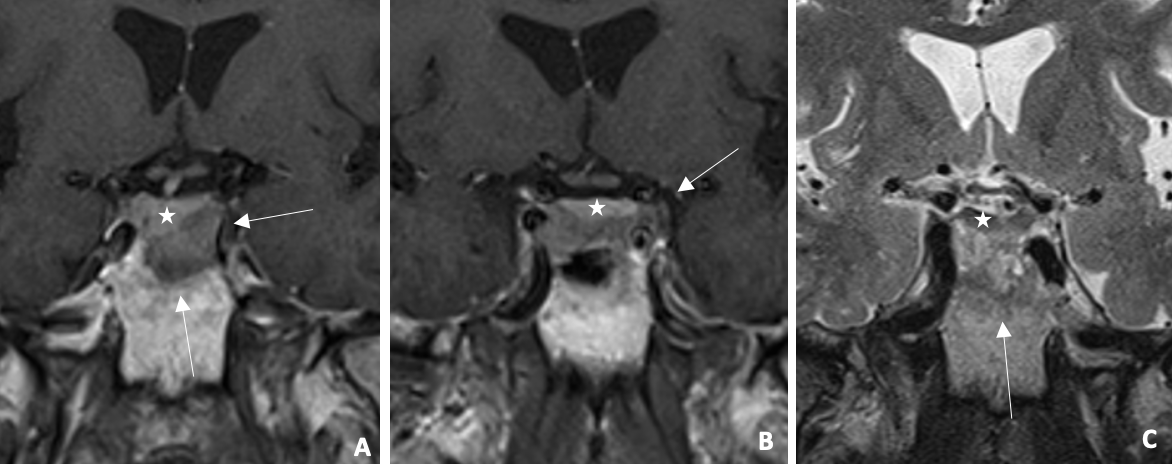

Figure 1

Infiltrative lesion (arrow) centered on the sellar region (A–B) Coronal post‑constrat T1WI: right deviation of pituitary stalk and pituitary gland (star). (C) Coronal T2WI: heterogeneous lesion , adjacent to hypointense pituitary gland. MRI shows infiltrative sellar lesion displacing pituitary stalk/gland.